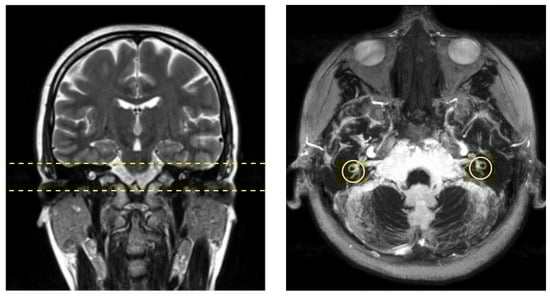

MRI studies were performed on a 3T whole-body scanner (Trio TIM, Siemens AG, Erlangen, Germany) using a 32-channel head array. First, a T2 weighted 2D fast spin-echo (FSE) sequence was employed to acquire anatomical images in coronal orientation, which were subsequently used to localize the high-resolution scan.

High-resolution images were acquired using a three-dimensional Fourier transformation constructive interference in steady state (3DFT-CISS) gradient-echo sequence [16] in axial oblique orientation with the imaging parameters shown in Table 1.

The slab was positioned to include the inner ear, based on the FSE localizer (Figure 1).

Figure 1. Subject imaging acquisition example: (left) volunteer coronal FSE localizer. Dashed straight yellow lines delimit the slab where the CISS-3D sequence was applied; and (right) cumulative projection of the CISS-3D sequence that includes the vestibular system, where semicircular ducts can be easily detected. The yellow circumferences denote the region where our study was conducted.